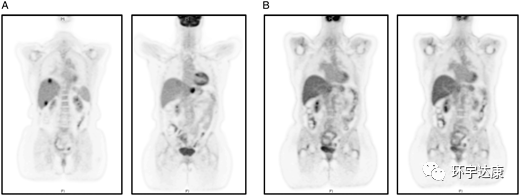

M女士,61岁,被确诊为胰腺导管癌,在胰腺体内有一个2.5cm的肿块,肝脏上有1.2cm的转移病灶,基因检测发现M女士存在NTRK1基因融合阳性,在接受拉罗替尼治疗后,胰腺和肝脏的病灶都明显缩小。

PET-CT扫描:(A)治疗前(B)拉罗替尼治疗后